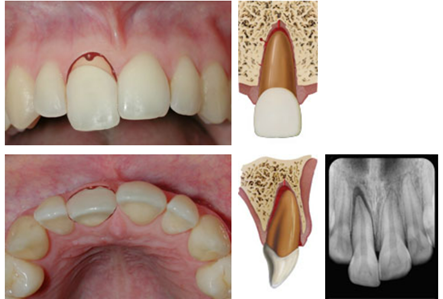

dx extrusion

A

Appears elongated

Excessively mobile

Usually lack of response except for teeth with minor displacements. The test is important in assessing risk of healing complications. A positive result to the initial test indicates a reduced risk of later pulp necrosis.

* In immature, not fully developed teeth, pulpal revascularization usually occurs. In mature teeth pulp revascularization sometimes occurs.

Occlusal, PA and 2 eccentric exposures from different horizontal angulations

Inc PA ligament space